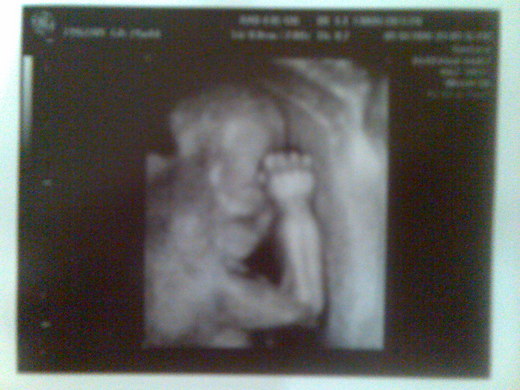

我們家

baby是個害羞的寶寶,

之前夾著腿不給看是弟弟或妹妹,

現在手手又擋著臉不給看,

baby~~~不要害羞嘛!

媽媽看看啊~

哎!我們家

baby不是害羞啦~

是愛搞笑,

現在的手勢是YA~